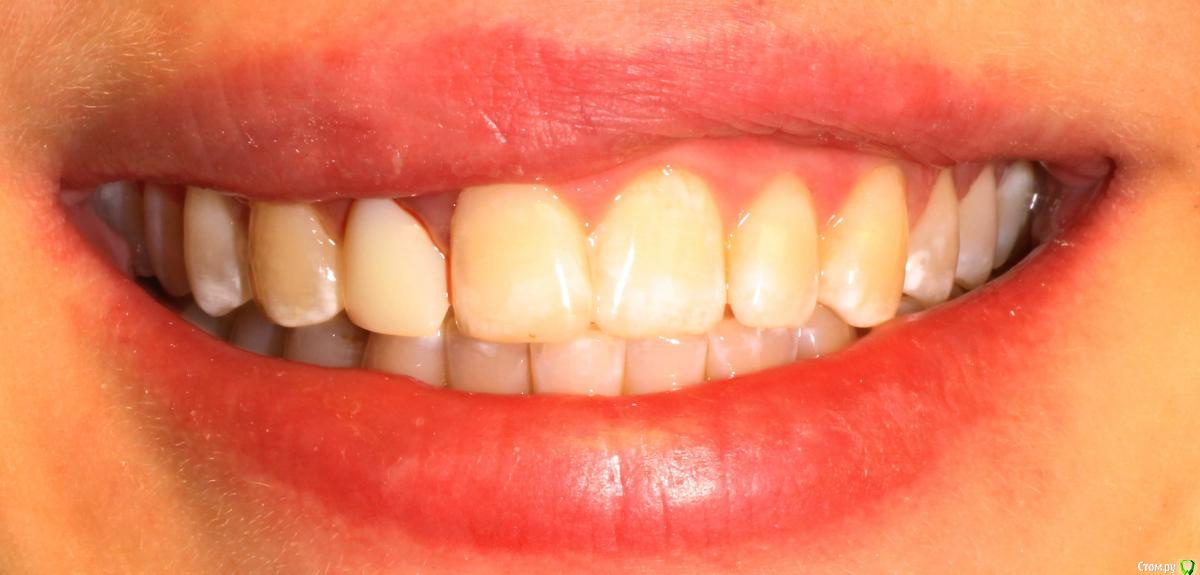

MenshikovDV Опубликовано 2 апреля, 2015 Поделиться Опубликовано 2 апреля, 2015 (изменено) Зуб 1.2 отлом коронковой части зуба, на период ожидания приема у хирурга и ортопеда (2 дня) приклеен к соседям. Вся процедура в одно посещение. Где-то часа два. Я ортопед, хирургия не моя, фото мои Изменено 2 апреля, 2015 пользователем MenshikovDV 19 Ссылка на комментарий

Alexey Doc Опубликовано 5 апреля, 2015 Поделиться Опубликовано 5 апреля, 2015 Класс! Аккуратно сработали!Единственно, думаю что аугментации была бы желательна. Ссылка на комментарий

MenshikovDV Опубликовано 7 апреля, 2015 Автор Поделиться Опубликовано 7 апреля, 2015 Класс! Аккуратно сработали!Единственно, думаю что аугментации была бы желательна.Спасибо.Время покажет. Ссылка на комментарий